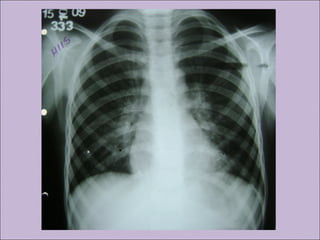

C) Anormalidades persistentes à radiografia de tórax

Manifestações sino-pulmonaresManifestações sino-pulmonares A)Colonização / infecção persistentes por patógenos típicos da FC como Staphylococcus aureus, Haemophilus influenzae, Pseudomonas aeruginosa e Burkholderia cepacia B) Tosse crônica e produtiva C) Anormalidades persistentes à radiografia de tórax D) Obstrução das vias aéreas E) Pólipos nasais, sinusite F) Baqueteamento digital Rosenstein. J Pediatr. 1998;132:389-95